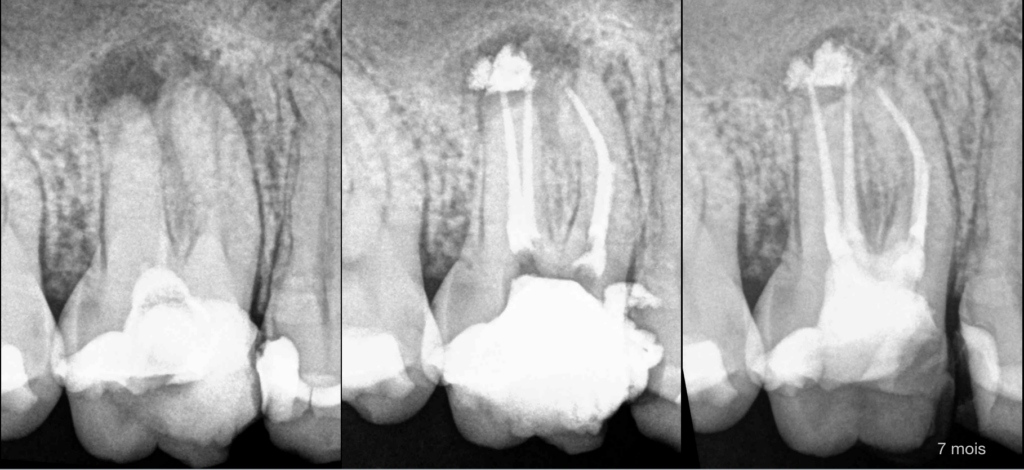

🔍 𝐍𝐞́𝐜𝐫𝐨𝐬𝐞 𝐩𝐮𝐥𝐩𝐚𝐢𝐫𝐞

Parodontite apicale symptomatique

💡 𝐓𝐫𝐚𝐢𝐭𝐞𝐦𝐞𝐧𝐭 𝐜𝐚𝐧𝐚𝐥𝐚𝐢𝐫𝐞

🗓️ À 7 mois : le traitement semble efficace du point de vue de la cicatrisation osseuse.